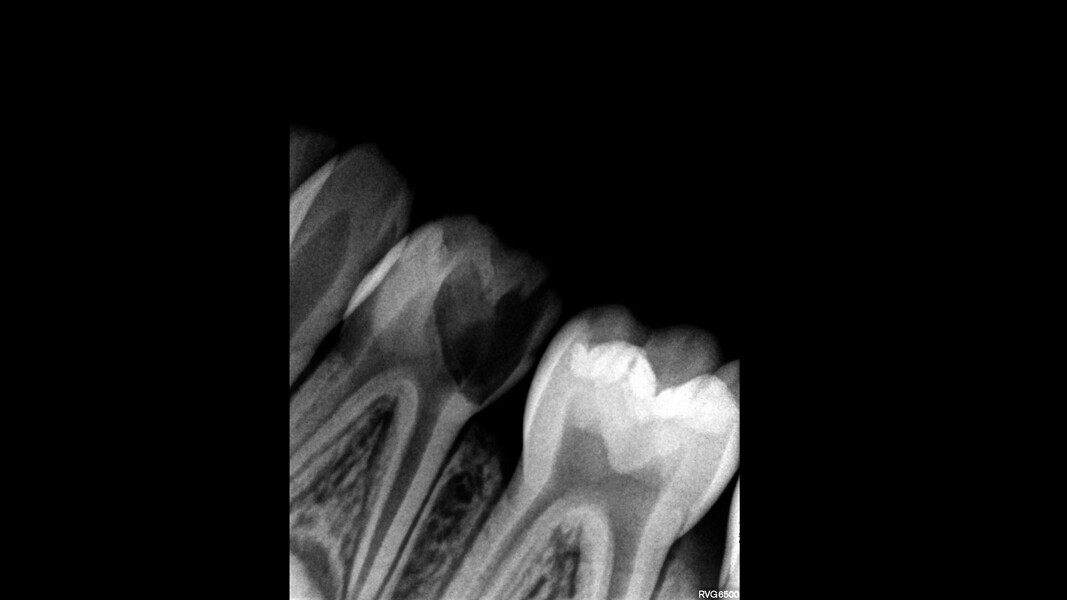

This male patient was 6 years and 7 months old and presented with severe tooth decay on the mandibular left first primary molar without any symptoms of pain. He experienced slight discomfort to percussion and palpation of the buccal gingiva. A buccal abscess and no mobility were observed. The radiograph showed a large area of interradicular bone loss. The tooth was diagnosed with pulp necrosis and an asymptomatic apical abscess. Pulpectomy was performed, and at a second appointment, a stainless-steel crown was placed upon confirming absence of signs or symptoms of disease. At the 14-month recall, no clinical pathology was detected and a normal eruptive process of the permanent premolars was observed in spite of the extrusion of the obturation material.